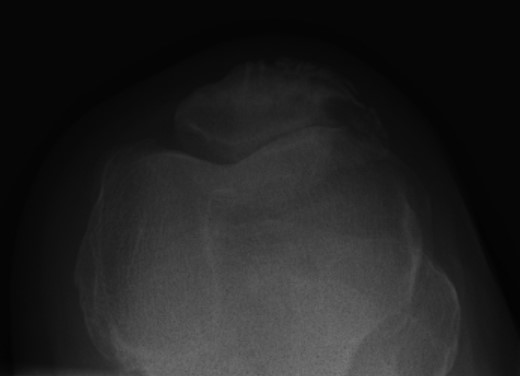

Nineteen months earlier the patient had consulted his general practitioner complaining of left knee pain. Radiographs performed at that time were reported to show joint space narrowing within the patello-femoral compartment as well as early joint space narrowing within the medial compartment. A subchondral lucency was also noted within the patella which was described as a subarticular cyst secondary to the previously mentioned patello-femoral degeneration (Figs 1–3).

The absence of associated features of systemic disease, as well as radiographic appearances in keeping with early patello-femoral osteoarthritis (OA), account for the delay in diagnosis. The initial images suggest mild degeneration but, whilst subarticular cysts are a radiographic feature of OA, the lesion shown in this case is larger than would be expected with the level of disease shown elsewhere in the joint.